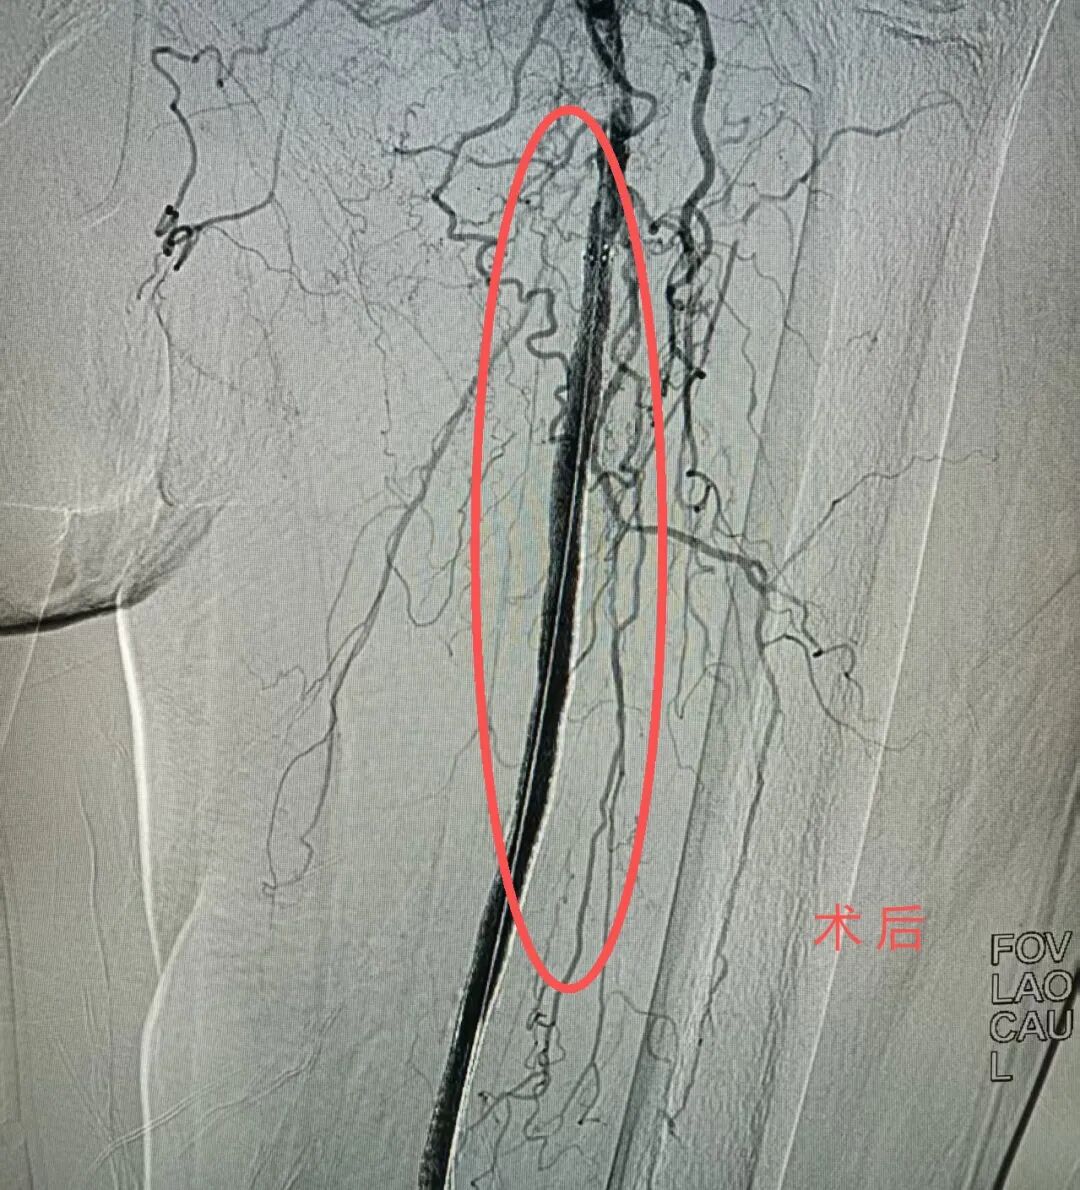

介入手术中,医生在患者左大腿根部进行仅2毫米的穿刺,将球囊导管精准送达闭塞血管部位,通过球囊扩张撑开狭窄段,恢复血流。术中患者全程保持清醒,术后左下肢皮温明显回升,疼痛显著缓解,足背动脉搏动恢复。该项技术避免了全身麻醉风险,减少手术创伤,尤其适合高龄、体弱、合并症多的患者。术后患者恢复迅速,第二天即可下床活动,腿部溃疡也开始愈合。